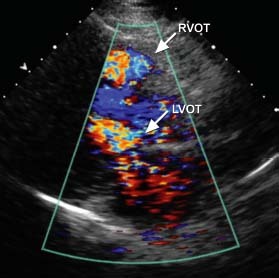

A 40-year-old man with known hypertrophic cardiomyopathy presented with syncope after coughing. Physical examination revealed a systolic murmur that was accentuated by the Valsalva maneuver. An electrocardiogram suggested biventricular hypertrophy and biatrial enlargement (Fig. 1). Echocardiograms revealed asymmetric septal hypertrophy with a diastolic septal thickness of 2.3 cm, and evidence of flow acceleration across the right ventricular outflow tract (RVOT) and left ventricular outflow tract (LVOT) (Figs. 2 and 3).

Fig. 2 Transthoracic echocardiogram (parasternal long-axis view) shows systolic flow acceleration across the right (RVOT) and left ventricular outflow tracts (LVOT).

Real-time motion image is available at www.texasheart.org/journal.